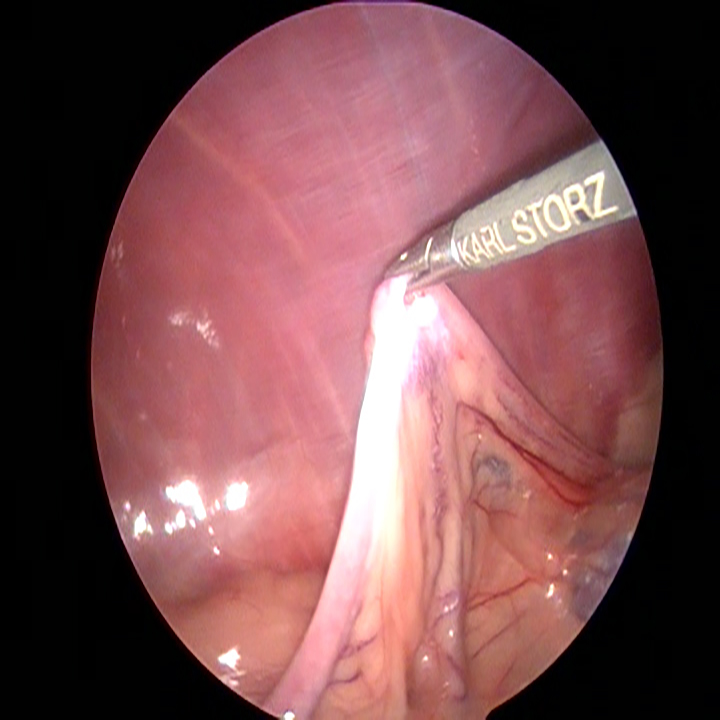

Wanneer alle trocars geplaatst zijn, kantelen we de operatietafel naar voren en leggen we de patiënt op haar zij. Dan gaan we op zoek naar de linker eierstok. Doordat de milt eroverheen ligt kan dit soms wat meer moeite kosten. Eenmaal gevonden, branden we de ophangbanden en bloedvaten van het ovarium door. Hierbij moet ervoor gezorgd worden dat er ver genoeg van de nieren en de buikwand af gewerkt wordt, om hitteschade te voorkomen. De eierstok wordt via het gat bij het bekken verwijderd. Na het controleren van de plek waar de eierstok verwijderd is en na het opnieuw plaatsten van de achterste trocar, wordt de andere kant gedaan.

De hond wordt hiervoor naar de andere kant gekanteld. De darmen moeten worden weggemasseerd en wanneer de eierstok gevonden is, herhaalt de procedure zich.

De daadwerkelijke laparoscopische sterilisatie, in beeld: